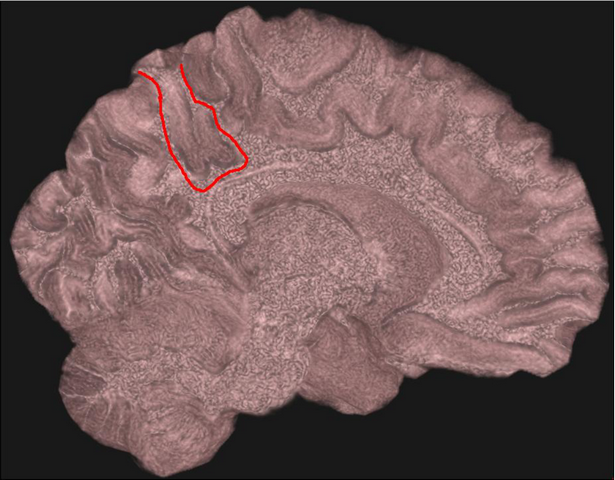

Студент четвертого курса факультета автоматики и вычислительной техники НГТУ НЭТИ Александр Грищенко и аспирант кафедры систем сбора и обработки данных Антон Герасимов разработали программу, которая позволяет создать объемное изображение мозга, — ранее удавалось рассмотреть лишь зоны на поверхности коры.

В первую очередь софт предназначен для клинической практики в качестве вспомогательного инструмента для визуализации МРТ-данных при диагностике, планировании операций и контроля динамики патологий. Также программное обеспечение может служить платформой для создания более специализированных аналитических инструментов.

«Программа позволяет не только выделять мозг и строить его объемное изображение, но и при необходимости выделять отдельные области мозга для анализа его внутренних структур — зон интереса», — рассказал разработчик и добавил, что в будущем планирует заняться вычислением массы мозга по снимкам МРТ на основе уже работающего софта.